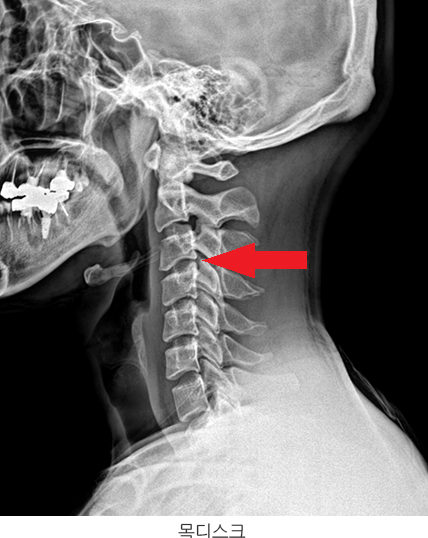

목디스크의 진단은 일반적으로 여러 가지 영상 촬영 기술을 통해 이루어집니다. 단순 방사선 검사를 통해 경추부의 전반적인 구조를 확인할 수 있으며, 더 구체적인 진단을 위해서는 자기공명영상(MRI)을 활용하여 디스크의 상태와 신경 압박 정도를 파악할 수 있습니다. 또한 컴퓨터 단층촬영(CT)을 통해 디스크의 경화 상태와 척추 뼈 구조를 정밀하게 살펴볼 수 있습니다.